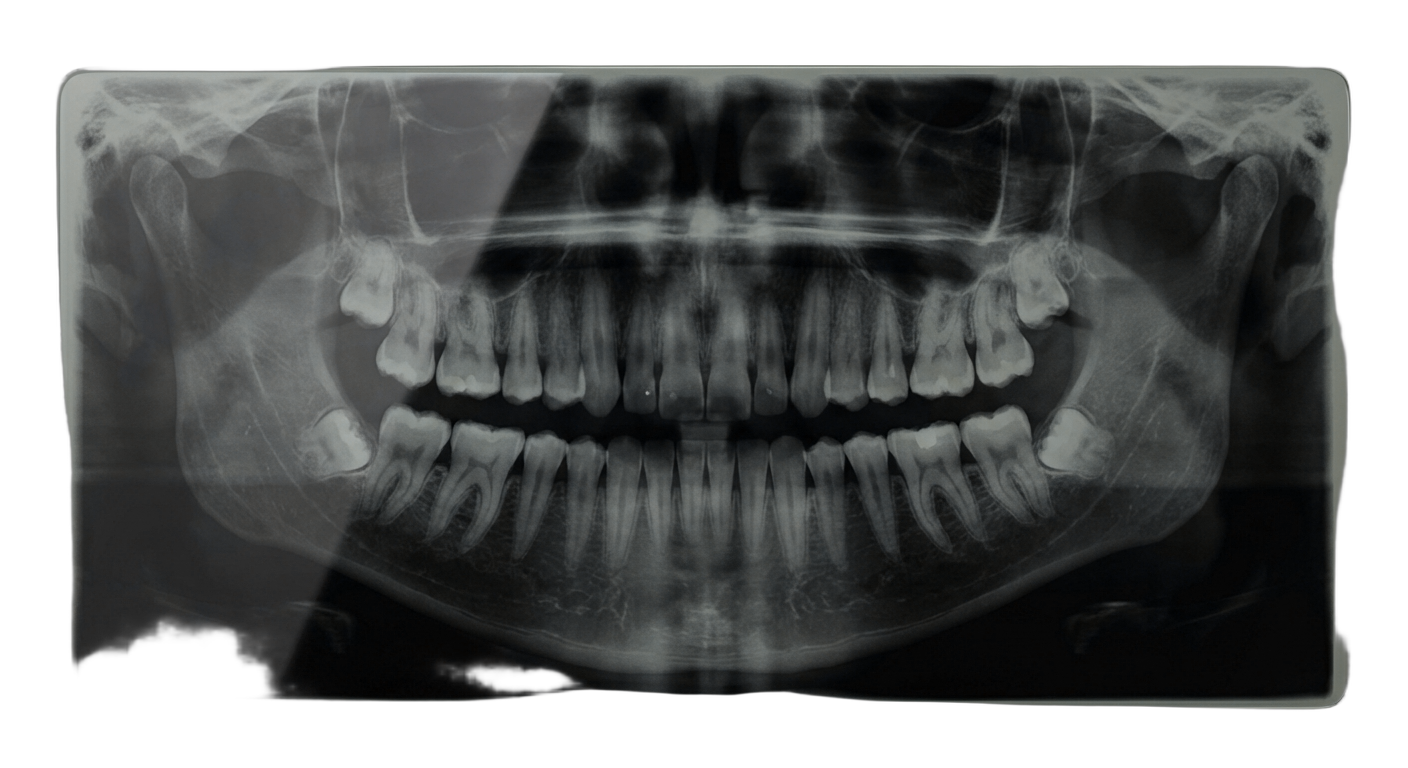

Если зуб разрушен менее чем на 50%, обычно достаточно прямой композитной реставрации или керамической вкладки. При разрушении более 50% рекомендуется коронка — она полностью покрывает зуб и защищает его от дальнейшего разрушения. Точный метод восстановления врач определит после осмотра и рентгеновского снимка.